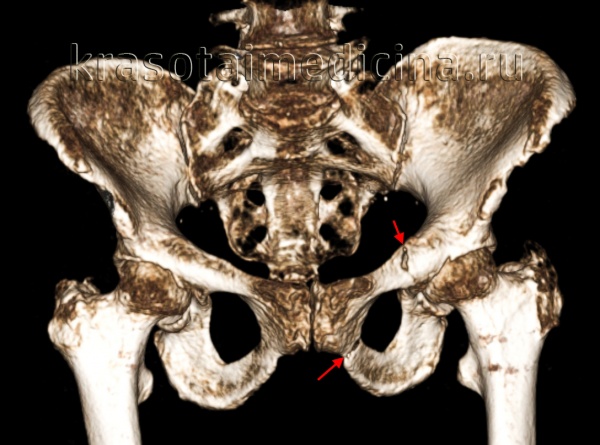

Для уточнения диагноза выполняют обзорную рентгенографию таза и рентгенографию поврежденного сустава в трех дополнительных проекциях. По возможности пациента направляют на КТ таза, поскольку эта методика позволяет более точно оценить тяжесть травмы и характер смещения отломков. Диагностическая ценность компьютерной томографии возрастает при повреждениях задней колонны и оскольчатых переломах.

Для исключения открытого перелома проводят вагинальное или ректальное исследование. Поскольку данная травма в 30% случаев сочетается с повреждением седалищного нерва, больным назначают консультацию невролога или нейрохирурга для точной оценки неврологического статуса.

Лечение перелома вертлужной впадины